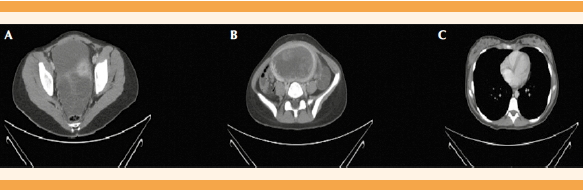

Se volvió a interrogar a la paciente, en presencia de su padre y representante legal, quien insistía en la ausencia de amenorrea y relaciones. Por lo tanto, se trataba de una paciente nuligrávida, con una masa uterina de gran tamaño y β-hCG superior a 1,000,000 UI/L. Opciones diagnósticas: mola hidatiforme, coriocarcinoma primario y tumor germinal. La radiografía de tórax se reportó normal y se amplió con una tomografía axial computada pélvica y torácica (Figura 2). En el corte pulmonar se evidenciaron cuatro nódulos, de 8 a 1.5 mm que sugerían metástasis pulmonares en virtud de los antecedentes de la paciente. En el corte pélvico se describió: gran masa, aparentemente ocupada por la cavidad uterina, heterogénea, con predominio de hipodensidad, con algunas áreas más hipercaptantes en el margen lateral derecho y posterior, de 114 x 64 x 123 mm, de aspecto tumoral: ovarios de gran tamaño con quistes tecaluteínicos (por estimulación ovárica), asociados a líquido libre en la pelvis en cantidad escasa. Se interconsultó con la Unidad de Oncología Pediátrica para tratar el caso, y se consensuó practicar un legrado uterino como método de biopsia, solicitar una resonancia magnética pélvica y craneal y marcadores tumorales. Los marcadores tumorales se reportaron normales, excepto el CA 125 que fue de 122 U/mL y la β-hCG que se había incrementado a 1.305.389 UI/L.

Figura 2 Tomografía axial computada. A y B. Imágenes de TAC de abdomen donde se observa una gran masa, de aspecto tumoral, al parecer ocupa la cavidad uterina, heterogénea, con predominio de hipodensidad, con algunas áreas más hipercaptantes en el margen lateral derecho y posterior. C. Imagen de TAC torácica en la que se observan nódulos pulmonares compatibles con metástasis.